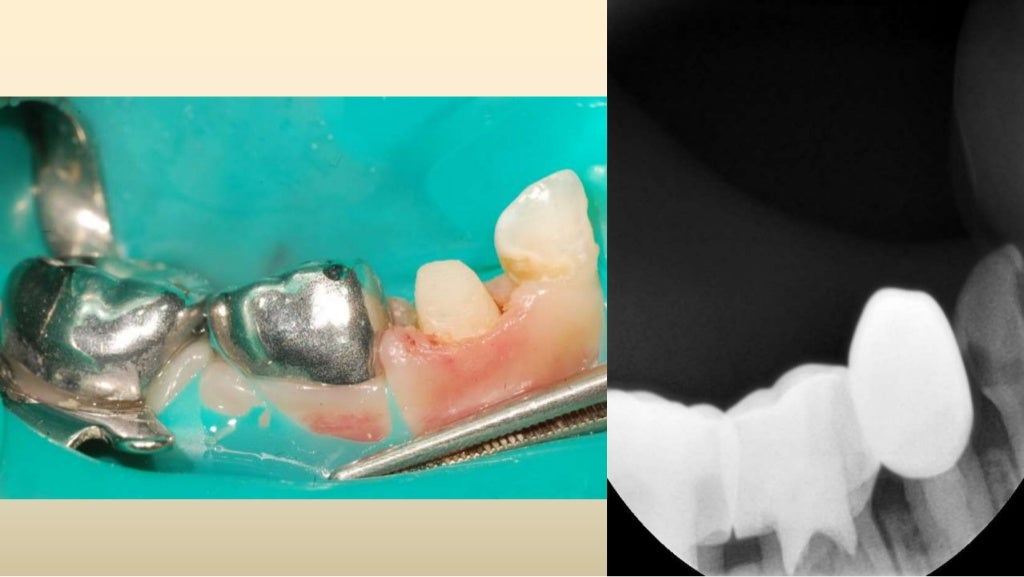

Anterior zirconia crown’s application technique. a Preoperative Zirconia Crown Slideshare The document outlines the various uses of zirconia in dentistry including crowns, bridges, implants, and more. The included studies reported that zirconia crowns for primary teeth were associated with better gingival and periodontal health, good. It also discusses challenges with bonding to. Monolithic zirconia primary crowns advantages • lifelike esthetics to rival custom laboratory fabricated crowns • proven durability in. Zirconia Crown Slideshare.